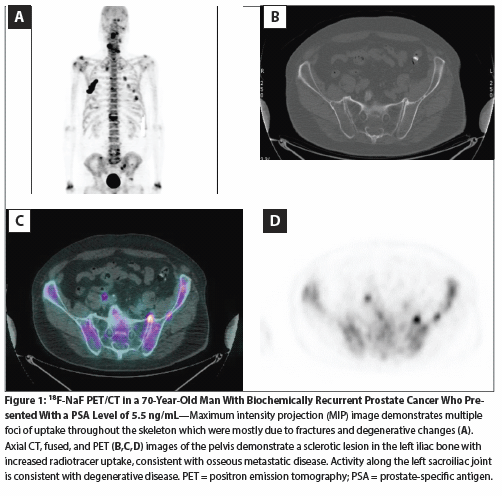

Figure 1: (18)F-NaF PET/CT in a 70-Year-Old Man With Biochemically Recurrent Prostate Cancer Who Presented With a PSA Level of 5.5 ng/mL

Yet, despite such data, false-positive scans remain a significant concern. The high number of false-positives is likely due to the steep learning curve associated with interpretation of this sensitive examination. Increased activity is seen in areas of increased perfusion and bone matrix, which would include both malignant and benign processes. The exam's specificity is increased through careful evaluation of the CT component to characterize areas of uptake on PET as either malignant or benign (eg, having etiologies such as degenerative disease or trauma).[7] Figure 1 demonstrates multiple foci of uptake that were for the most part due to post-traumatic and degenerative changes; however, there was a single focus of uptake in the left iliac bone that was consistent with an osseous metastasis. Adjacent activity in the sacroiliac joint, by contrast, was due to degenerative disease, which was confirmed on the CT component of the study.